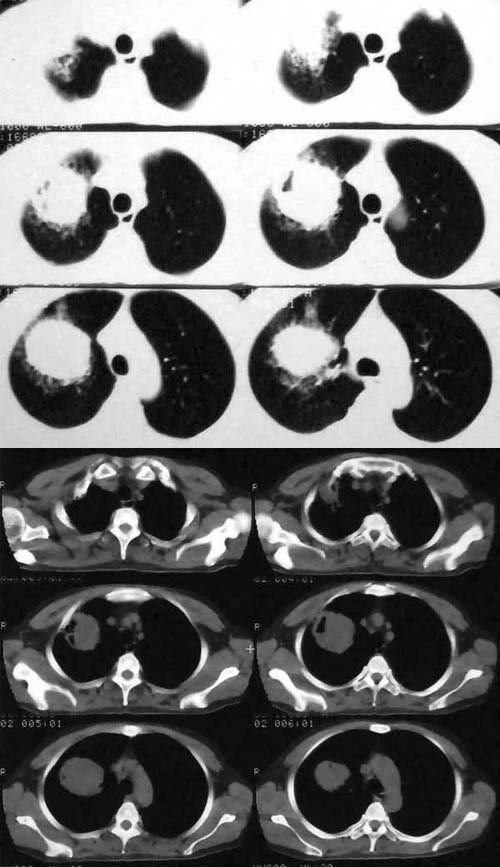

ct2209:guzhongliangddd提供 病理结果腺癌

男,42。体检偶然发现。纵隔肺门无增大淋巴结